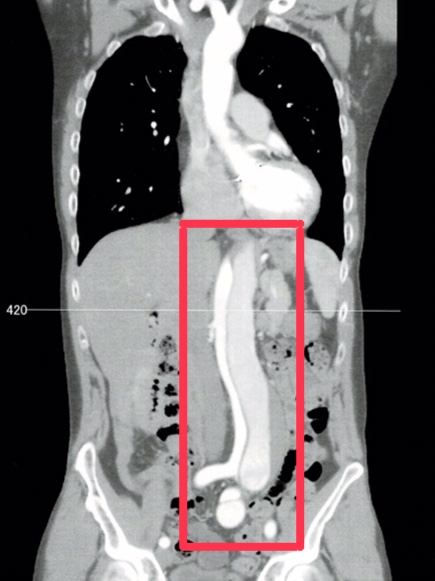

下の写真は手術を決定づけたCT画像。通常2cmと言われる腹部大動脈が解離した状態で倍以上に拡張している(赤枠内)。赤枠下半分に位置する部分は、本来の血液の流れである真腔(白色部分)、解離で裂けた血管内を流れる偽腔(薄い灰色)、それと淀んだ血液が偽腔内で固まっている部分(右端の濃い灰色)の3層になっていることがわかる。